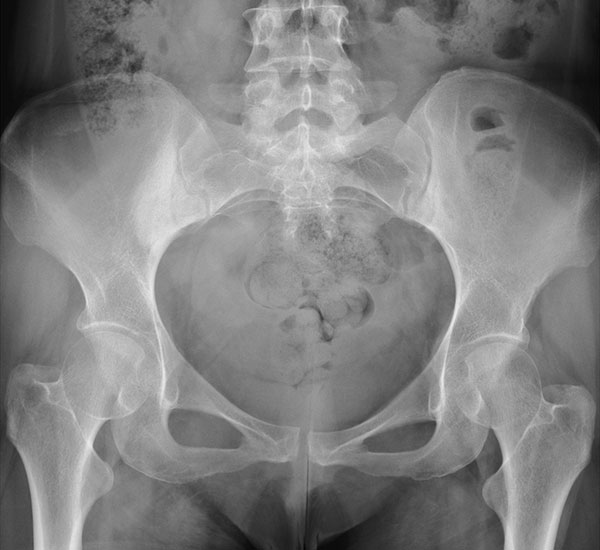

Diagnosing hip conditions involves a thorough evaluation that includes reviewing your medical history, assessing your current symptoms, and performing a detailed physical examination. During the exam, specific tests may be used to evaluate range of motion, joint stability, muscle strength, and areas of tenderness or discomfort. Imaging studies often play a key role in diagnosis. X-rays can help identify structural abnormalities or rule out fractures, while MRI or MR arthrogram can provide detailed images of soft tissues such as cartilage, tendons, and the labrum.